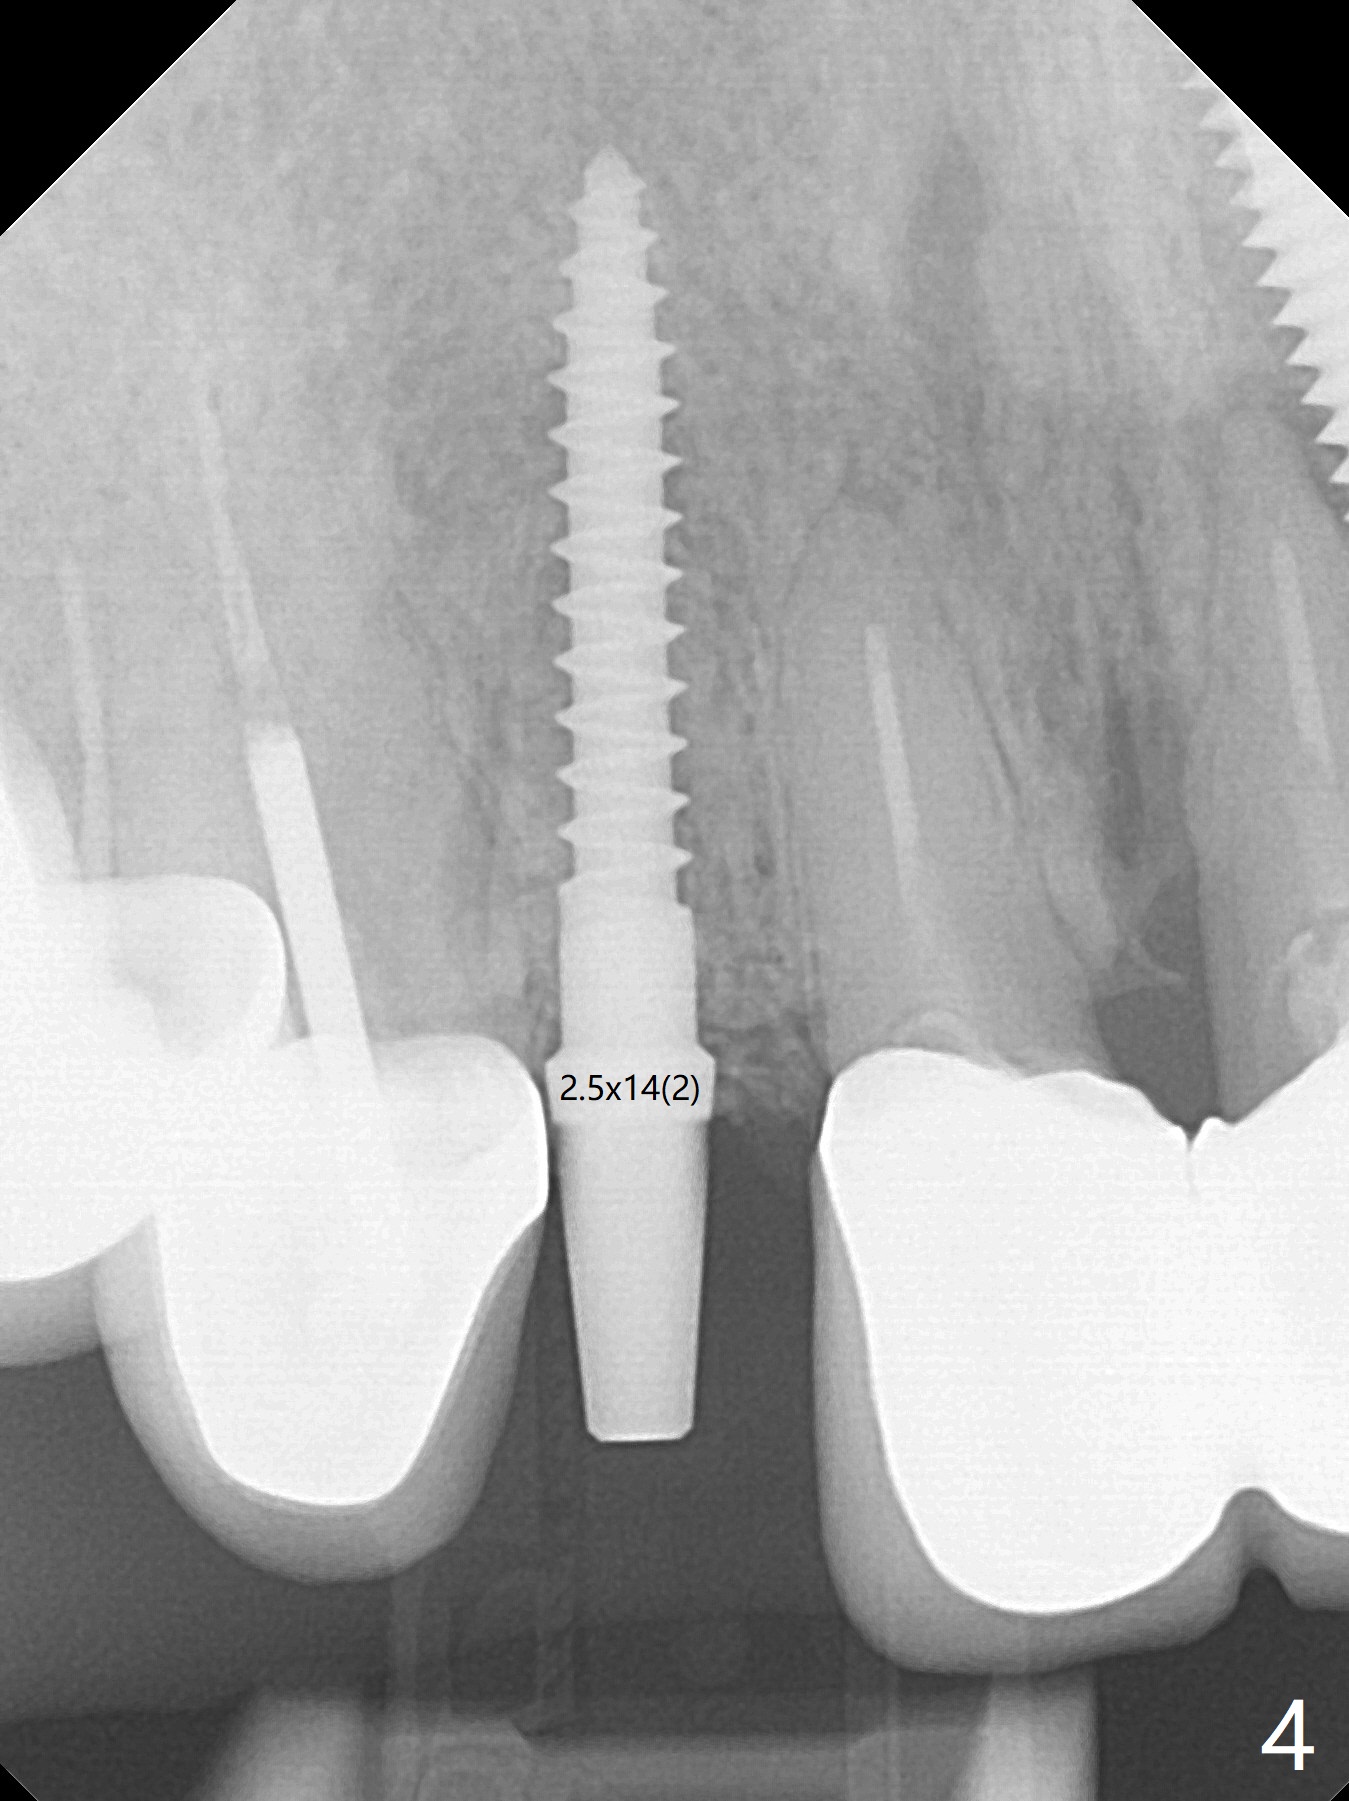

The edentulous area at #7 is narrow both buccopalatally and mesiodistally, whereas the crowns of the neighboring teeth are long (Fig.1,2). For the latter reason, it is difficult to remove the apical portion of the root, including gutta percha with surgical handpiece (Fig.3 *) for socket shield (Fig.2 *). To avoid the perspective implant touching socket shield, initial osteotomy is palatal. When a 2 mm drill is being used, the coronal end of the palatal plate starts to perforate. A 2.5x14 mm 1-piece implant is placed with 30 Ncm (Fig.4). The palatal plate is thin (Fig.5). Preop CT will help determine the position of initial osteotomy. The buccal gingiva seems to have been re-attached to the underlying alveolus and the provisional 1 month postop (Fig.6). The teeth #8 and 9 fracture (an implant is placed at #8 and bone graft at #9, while the implant at #7 is osteointegrating (Fig.7). In fact the shield is exposed without symptom. A year postop, another dental provider sends a photo of apparently hemorrhagic gingiva around #7 crown (Fig.8). A few days later with oral hygiene instruction, the gingiva around the exposed root piece is healthy (Fig.9). The root surface is reduced; with socket shield, there is no buccal plate collapse; in contrast the neighboring buccal plate (at #8 and 9) is concave (Fig.10). There is minimal exposure 11 days postop (Fig.11). The gingiva palatal to the shield is erythematous, a possible sign of periimplantitis. The socket shield at #7 appears to be fused with the buccal plate 11 months postop (Fig.12), as compared to the implant at #10 nearly 4 years postop (Fig.14). The buccopalatal widths at #7 and 10 are equivalent (Fig.13,15).